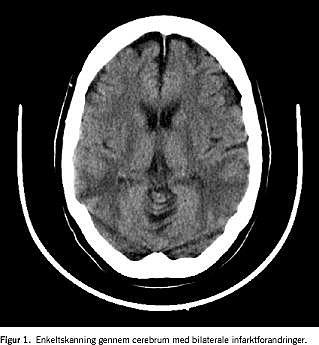

I det fjerde døgn ændredes patienten cerebralt, og der opstod krampeanfald, som blev behandlet med diazepam og valproat. En computertomografi (CT) af cerebrum viste bilaterale symmetriske iskæmiske områder på overgangen mellem a. cerebri media og a. cerebri posteriors forsyningsgebet, hvilket blev fortolket som hypoksisk encefalopati (Figur 1). En elektroencefalografi (EEG) viste svært abnorme forhold. En transkranial Doppler-sonografi var uden tegn på abnormt flowmønster og gav ikke mistanke om rebound vasospasmer eller cirkulationsstop i de større intracerebrale kar.